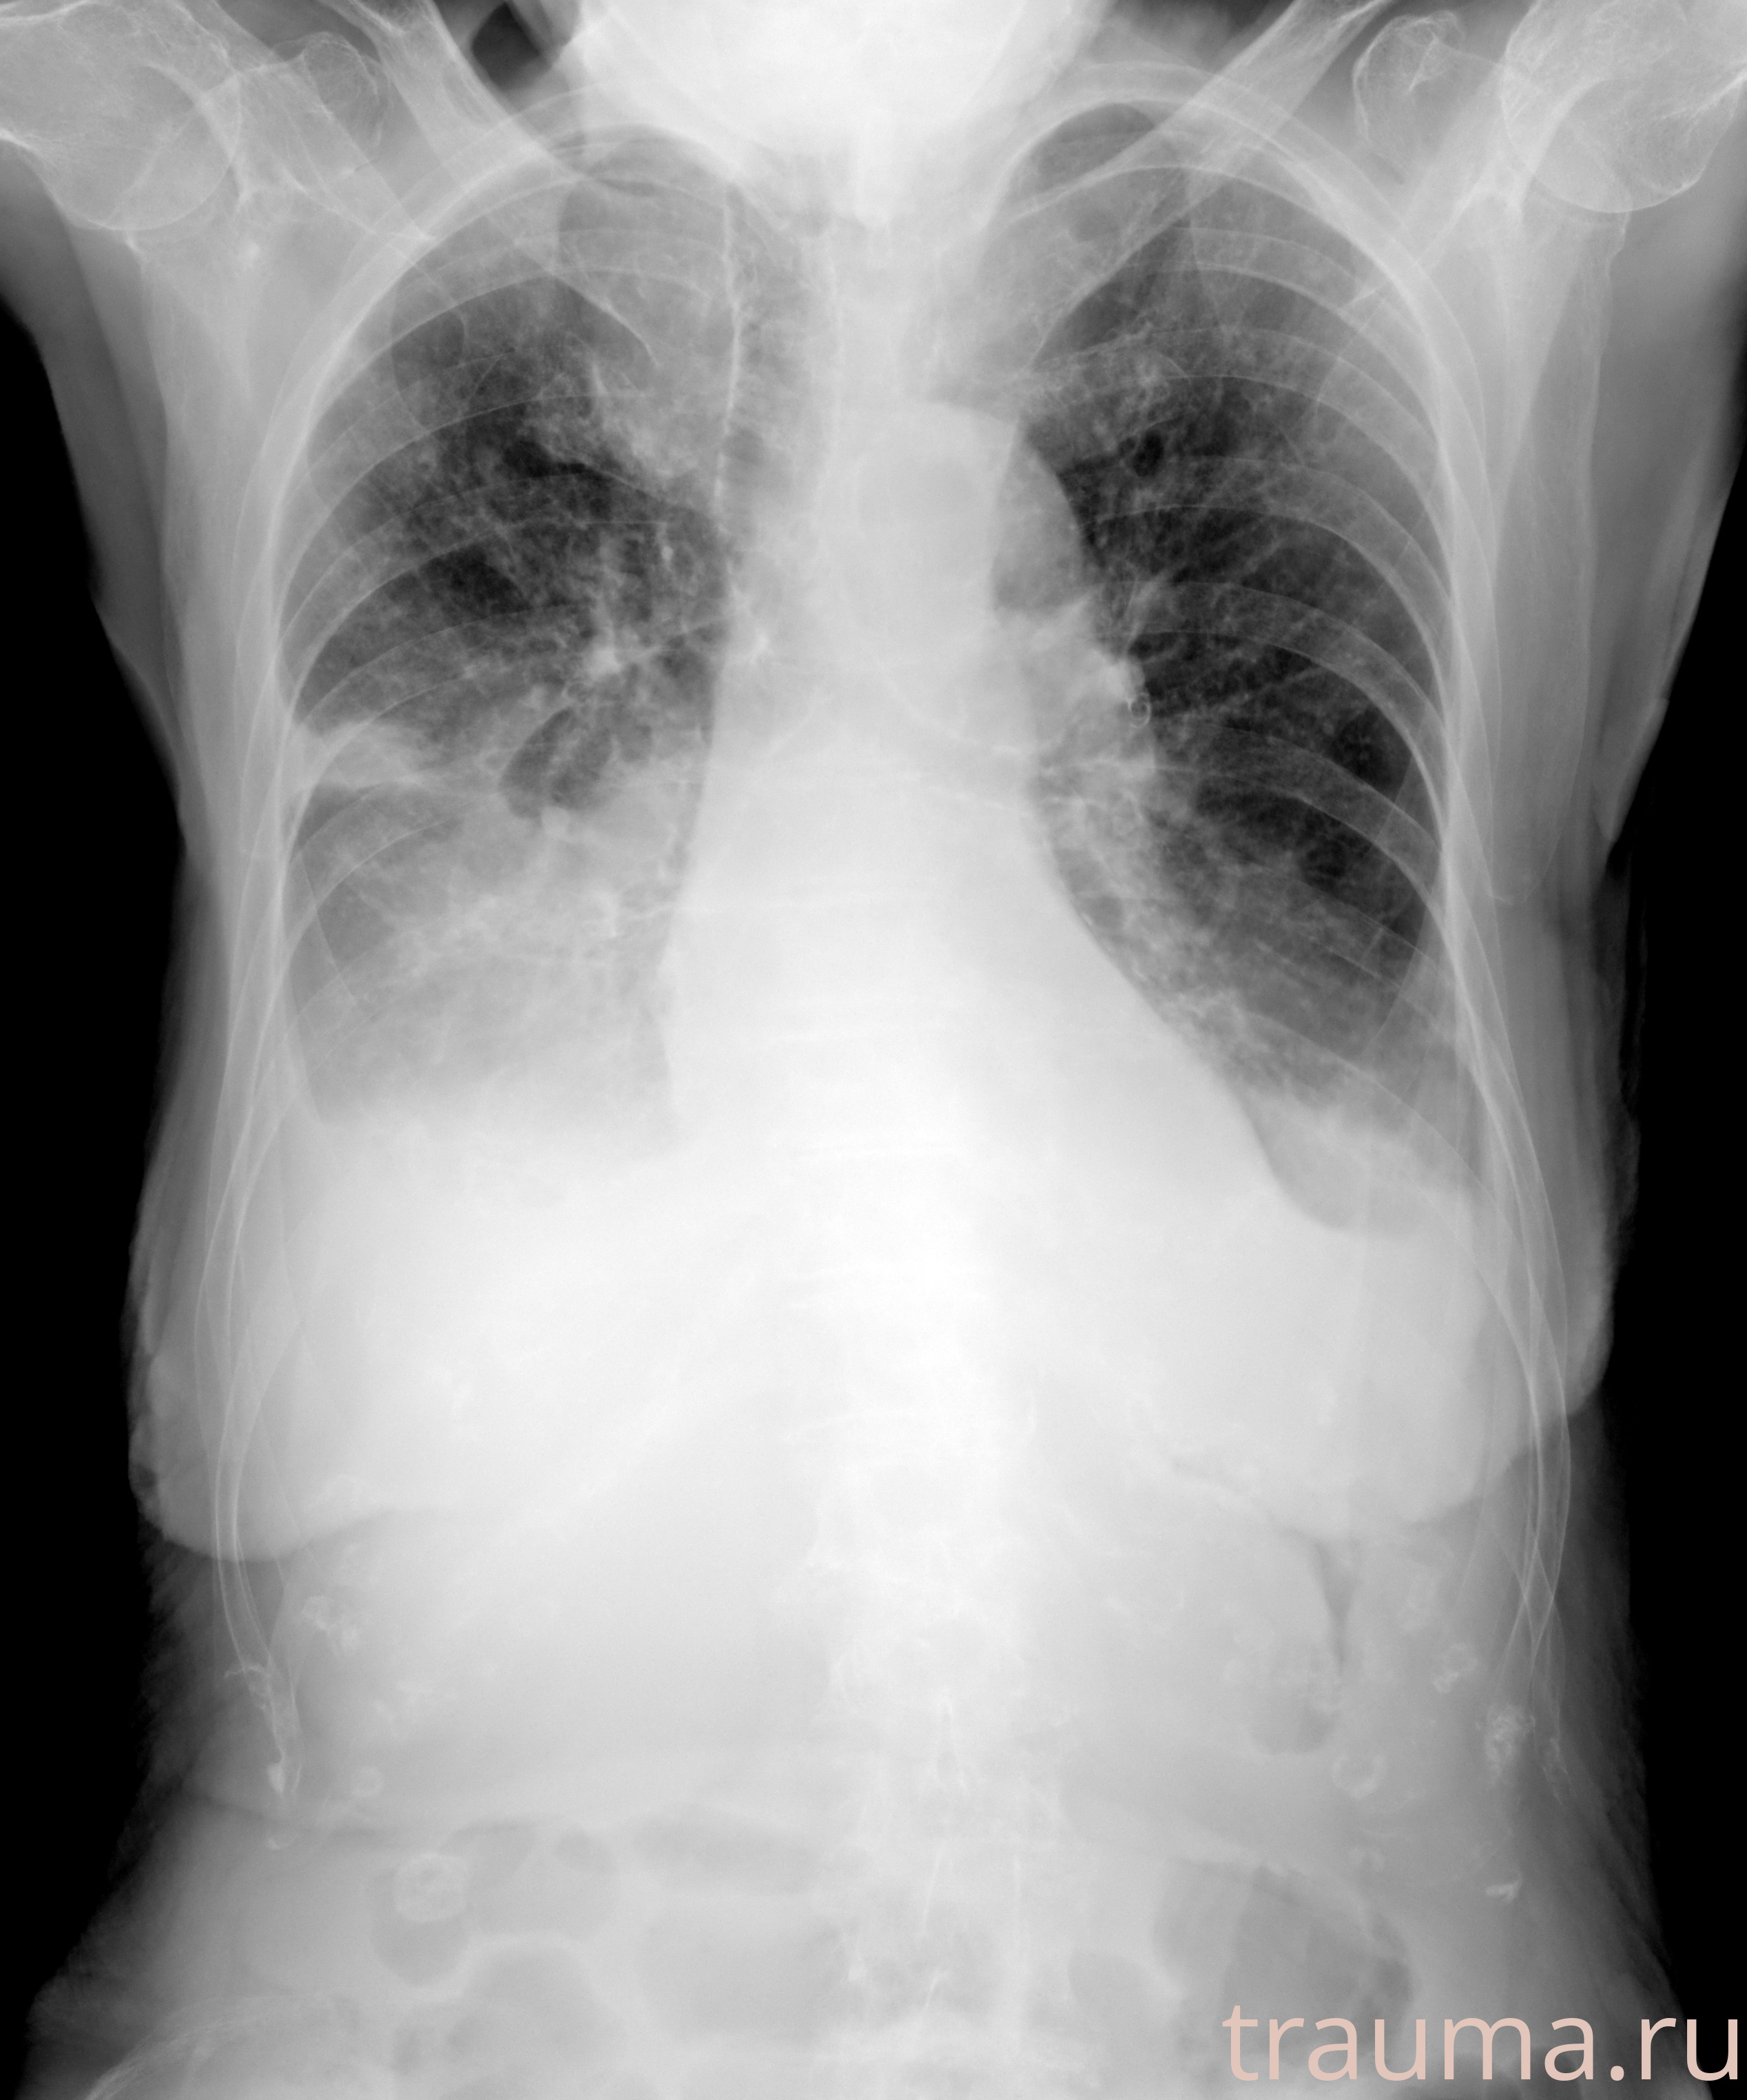

Рентген на дому: по вашему адресу приезжает врач-рентгенолог, травматолог-ортопед с мобильным рентгеновским аппаратом, проводит диагностику травмы или заболевания, делает необходимые рентгенограммы, дает рекомендации по дальнейшему лечению. Получить качественные снимки в домашних условиях возможно благодаря уникальной методике, разработанной МосРентген Центром для института  Склифосовского

при переломе шейки бедра и пневмонии от компании МосРентген Центр - партнера Института имени Склифосовского